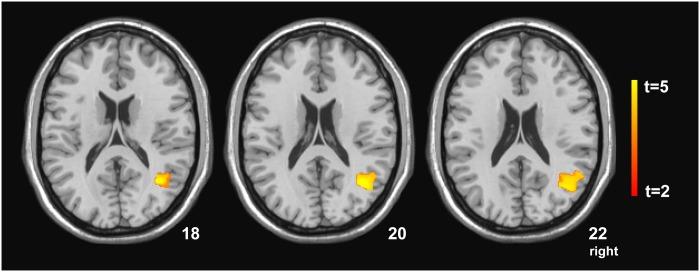

Acquisition of numerical knowledge and understanding of numerical information are crucial for coping with the changing demands of our digital society. In this study, we assessed arithmetic learning in older and younger individuals in a training experiment including brain imaging. In particular, we assessed age-related effects of training intensity, prior arithmetic competence, and neuropsychological variables on the acquisition of new arithmetic knowledge and on the transfer to new, unknown problems. Effects were assessed immediately after training and after 3 months. Behavioural results showed higher training effects for younger individuals than for older individuals and significantly better performance after 90 problem repetitions than after 30 repetitions in both age groups. A correlation analysis indicated that older adults with lower memory and executive functions at baseline could profit more from intensive training. Similarly, training effects in the younger group were higher for those individuals who had lower arithmetic competence and executive functions prior to intervention. In younger adults, successful transfer was associated with higher executive functions. Memory and set-shifting emerged as significant predictors of training effects in the older group. For the younger group, prior arithmetic competence was a significant predictor of training effects, while cognitive flexibility was a predictor of transfer effects. After training, a subgroup of participants underwent an MRI assessment. A voxel-based morphometry analysis showed a significant interaction between training effects and grey matter volume of the right middle temporal gyrus extending to the angular gyrus for the younger group relative to the older group. The reverse contrast (older group vs. younger group) did not yield any significant results. These results suggest that improvements in arithmetic competence are supported by temporo-parietal areas in the right hemisphere in younger participants, while learning in older people might be more widespread. Overall, our study indicates that arithmetic learning depends on the training intensity as well as on person-related factors including individual age, arithmetic competence before training, memory, and executive functions. In conclusion, we suggest that major progress can be also achieved by older participants, but that interventions have to take into account individual variables in order to provide maximal benefit.